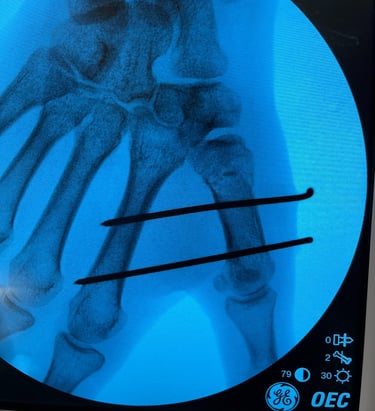

Polso e Mano

Mi occupo del trattamento delle principali patologie della mano e del polso, sia degenerative che traumatiche. Tratto condizioni frequenti come sindrome del tunnel carpale, dito a scatto, tendiniti e traumatologia della mano e del polso, con approccio conservativo o chirurgico mirato al recupero della funzionalità e alla riduzione del dolore.